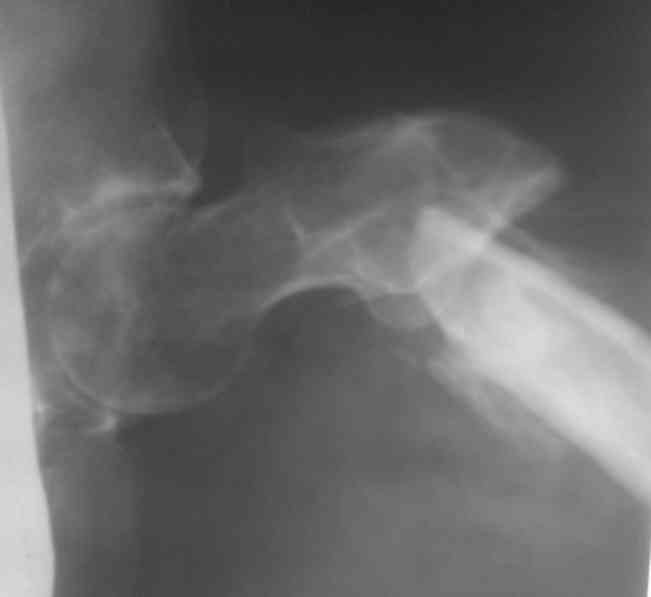

Re: Лечение ложного сустава шейки бедра

Название темы- это произвольно!! Второй снимок прилагаю!!!

Спасибо за второй снимок.

по поводу соображения!!! Будем идти в два этапа:вероятно будем растягивать ложняк на столе Хоули с учётом ротаций, идти открыто,фиксировать пластиной в шейку- добится консолидации, а затем удлиним в аппарате!!Или сразу Аппарат????

По-моему, этот план самый трудоемкий и травматичный. Если наложить сейчас аппарат закрыто, все за 2-3 недели исправить в аппарате, а вторым этапом зафиксировать отломки пластиной, с пластикой или без - решить по снимкам перед этим. Пластинку при восстановленной заранее анатомии делать будет нетрудно, не надо будет скелетировать и мобилизовать отломки.

Думаю, что устранять Все виды смещения в аппарате не менее трудоемко, чем одномоментная попытка синтеза пластиной, хотя более безопасно для пациента. Оптимальным видится решение этапной гиперкоррекции в дистракторе по длине. Добившись Достаточной подвижности между отломками уже на столе можно утранять по ширине джойстиками и ротационное на гвозде. Если нет опыта дистального блокирования сплошных гвоздей без ЭОПа, используйте каннюлированный в обязательном порядке.